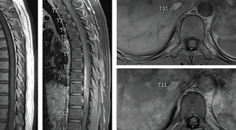

Case Report: Longitudinally Extensive Transverse Myelitis

Ylec Mariana Cardenas, MD; Lakshmi Leishangthem, MDYlec Mariana Cardenas, MD; Lakshmi Leishangthem, MD - Stroke